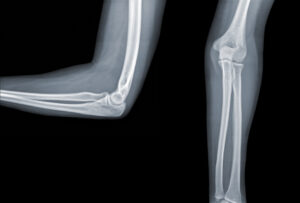

Armbågens uppbyggnad

Armbågen består av tre leder. En ledkapsel omsluter dessa leder. Rörelser som sker i armbågsleden är böjning och sträckning. Samt vridning inåt och utåt. Böjning och sträckning sker mellan överarmsbenet och armbågsbenet. Vridningar sker mellan armbågsbenet och strålbenet.